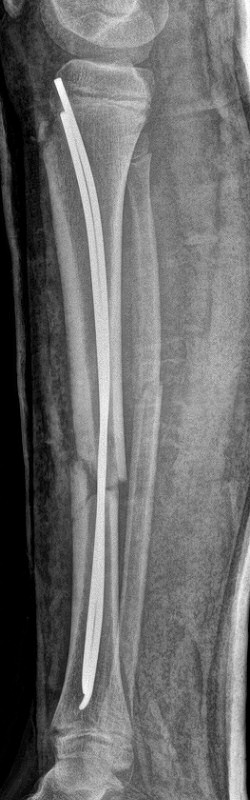

Tibia och fibula-frakturer, tibia spikats med 2 TEN-spik, sista 2 bilderna efter 5 veckor, då inte alls ömmande över frakturerna.